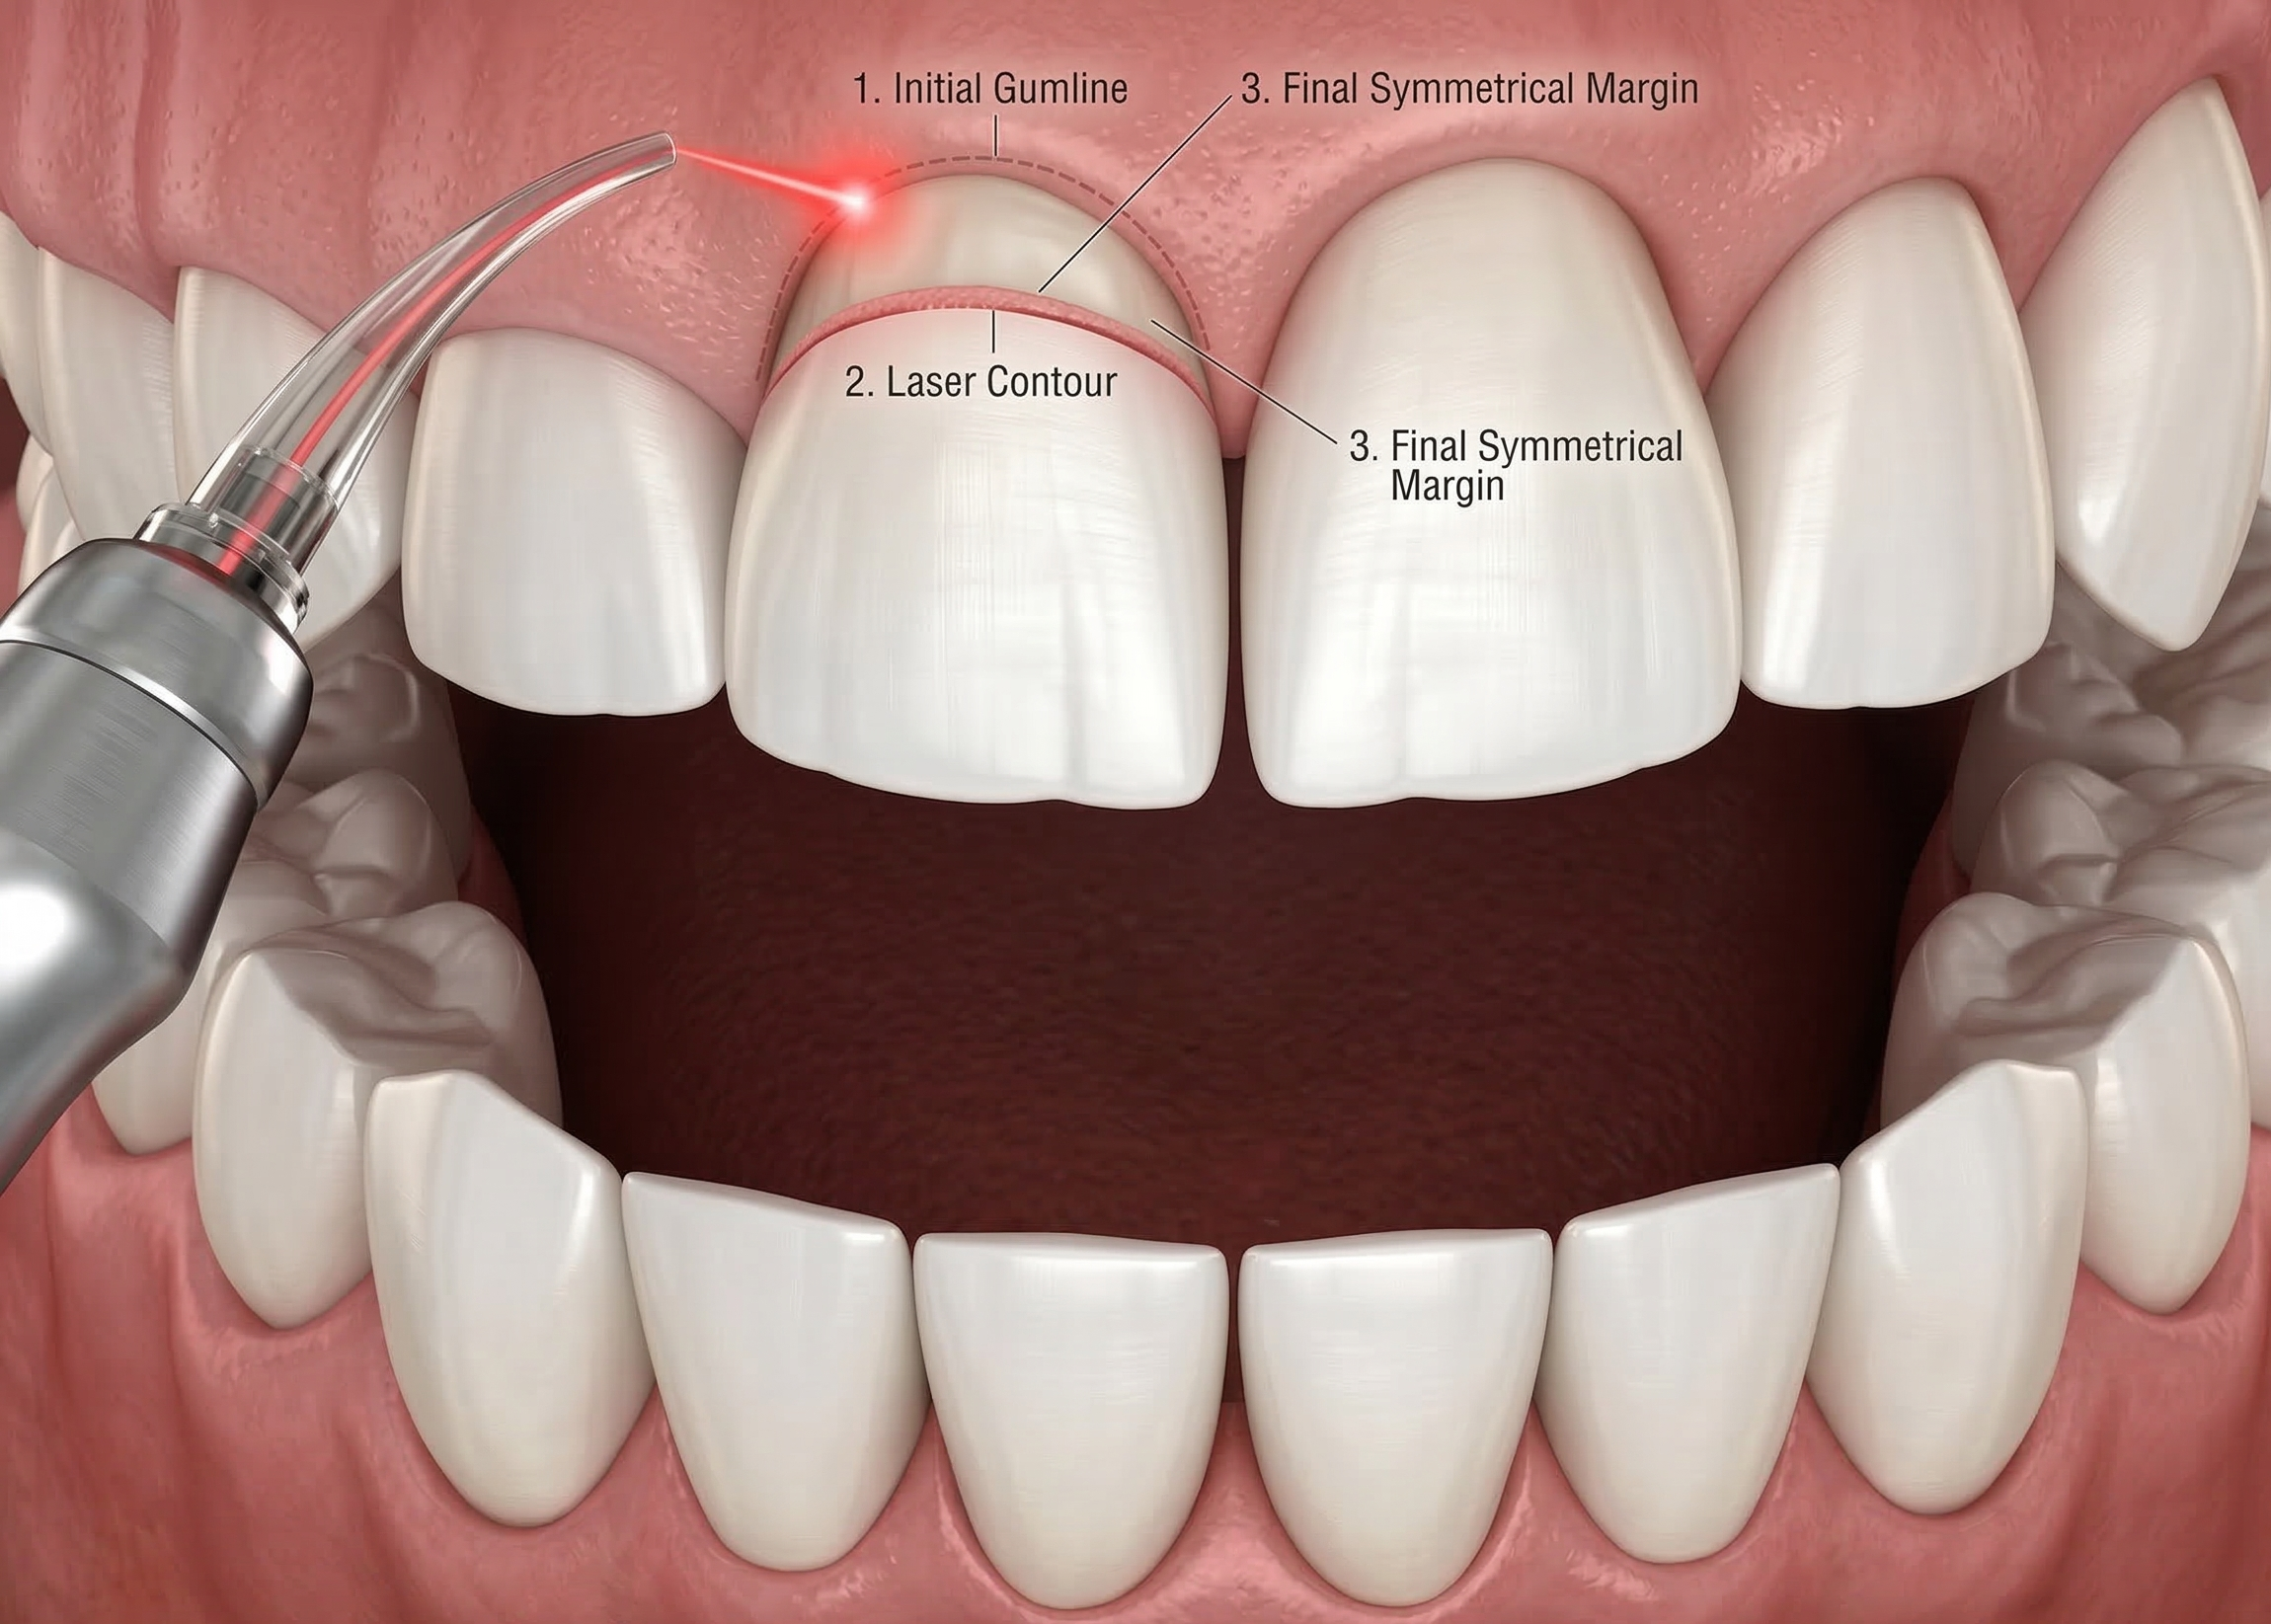

Laser Gum Recontouring – Minor Surgery In Chennai

Laser Gum Recontouring, also known as a laser gingivectomy or “gum lifting,” is a precise minor surgical procedure used to reshape and sculpt the gum line. Using advanced laser technology, our surgeons remove excess or uneven gum tissue to create a more balanced, symmetrical, and aesthetic smile.

Whether you are dealing with a “gummy smile” or an uneven gum line that makes your teeth look asymmetrical, laser recontouring offers a bloodless, painless, and rapid solution. This Laser Gum Recontouring minor surgery in Chennai is performed with expert care at Best Dental Clinic – Dr. N. Deenadayalan (T. Nagar) and Dr. Julian’s Laser Dental Clinic (Tambaram).

When is Laser Gum Recontouring Needed?

While often sought for cosmetic reasons, gum recontouring also serves functional health purposes. It is recommended for:

-

Gummy Smile Correction: When excessive gum tissue covers too much of the teeth, making them appear short or “boxy.”

-

Uneven Gum Line: To level the gums if they sit higher on some teeth and lower on others.

-

Periodontal Health: Removing “pockets” where bacteria trap easily, making it easier to maintain oral hygiene.

-

Preparation for Crowns or Veneers: To ensure the gum line is perfectly positioned before placing aesthetic restorations.